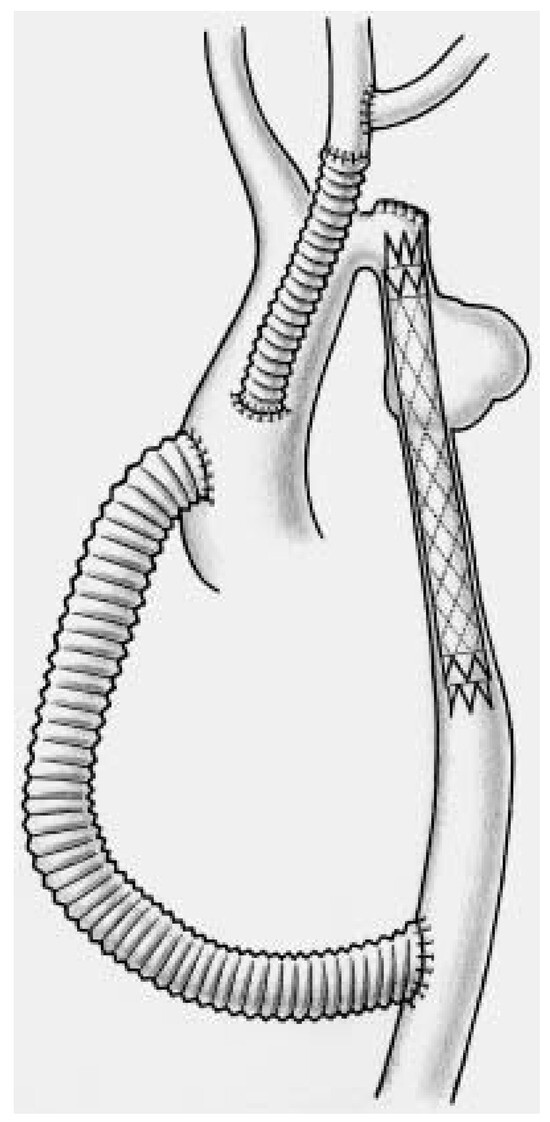

Une patiente de 31 ans souffrant d’une cardiopathie congénitale consulte car elle souhaite une grossesse [...]